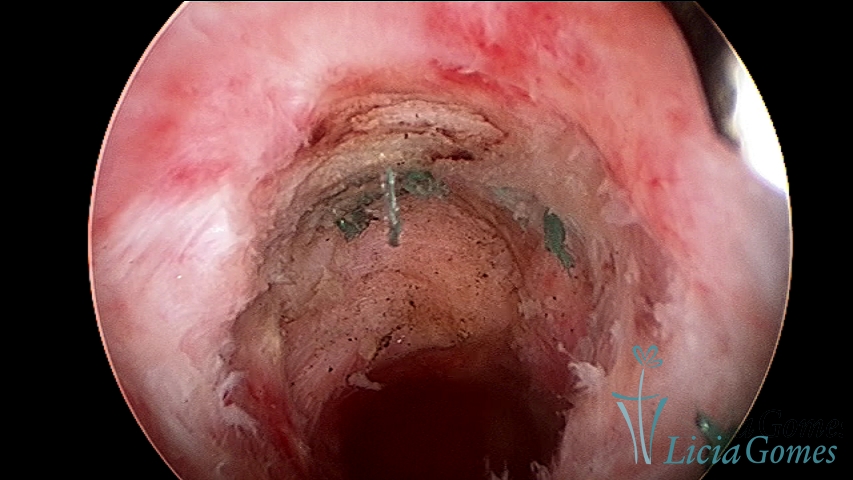

Após a ressecção do fio de sutura em retração da cicatriz de cesárea com fio de sutura